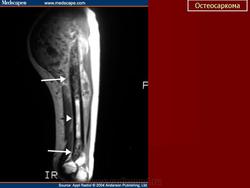

Рентгенологическая картина. Типичной картиной является наличие очага смешанной деструкции кости с разрушением кортикальной пластинки и формированием мягкотканного компонента опухоли. В процессе роста опухоли, периост приподнимается или отслаивается от коркового слоя, это вызывает новое костеобразование, обычно проксимальнее основного узла, данное явление получило название козырька Кодмана. Зона поражения на рентгеновском снимке имеет различную плотность, а характер матрикса часто облаковидный. КТ и МРТ могут играть важную роль в определении распространенности опухолевого процесса. Радионуклидное сканирование скелета выявляет «skip» метастазы, многоузловые опухоли, системное поражение. В ряде клиник принято использовать артериографию, так как остеосаркомы - гиперваскуляризованные опухоли.

Диагностика. Ведущим диагностическим методом, наряду с клиникой, является рентгенография. Характерно наличие очага деструкции кости, не имеющего четких контуров. Отсутствует зона склероза вокруг очага деструкции. Кортикальный слой кости разрушен. Сравнительно рано выявляется выход опухоли в окружающие мягкие ткани. Выделяются центральная и периферическая формы, а по характеру очага деструкции: остеолитическая — бесструктурный очаг разрушения кости, остеопластическая форма — очаг деструкции с участками склероза и уплотнения, смешанная форма — сочетание участков остеодитической и остеопластической форм. Во всех случаях очаг деструкции не имеет четких контуров. Характерна периостальная реакция в виде козырька Кодмэна или спикулообразного (игольчатого) периостита. В экстраоссальном компоненте опухоли возможны участки оссификации (патологическое костеобразование). На ранних стадиях заболевания опухоль может проявляться центрально или эксцентрически расположенным литическим очагом деструкции небольших размеров, с нечеткостью контуров кортикального слоя на ограниченном протяжении. Деструкция быстро нарастает и уже через 2-3 недели определяются вышеописанные типичные рентгенологические симптомы. Патологические переломы чаще наблюдаются при литических формах.. Характерно гематогенное метастазирование в легкие.